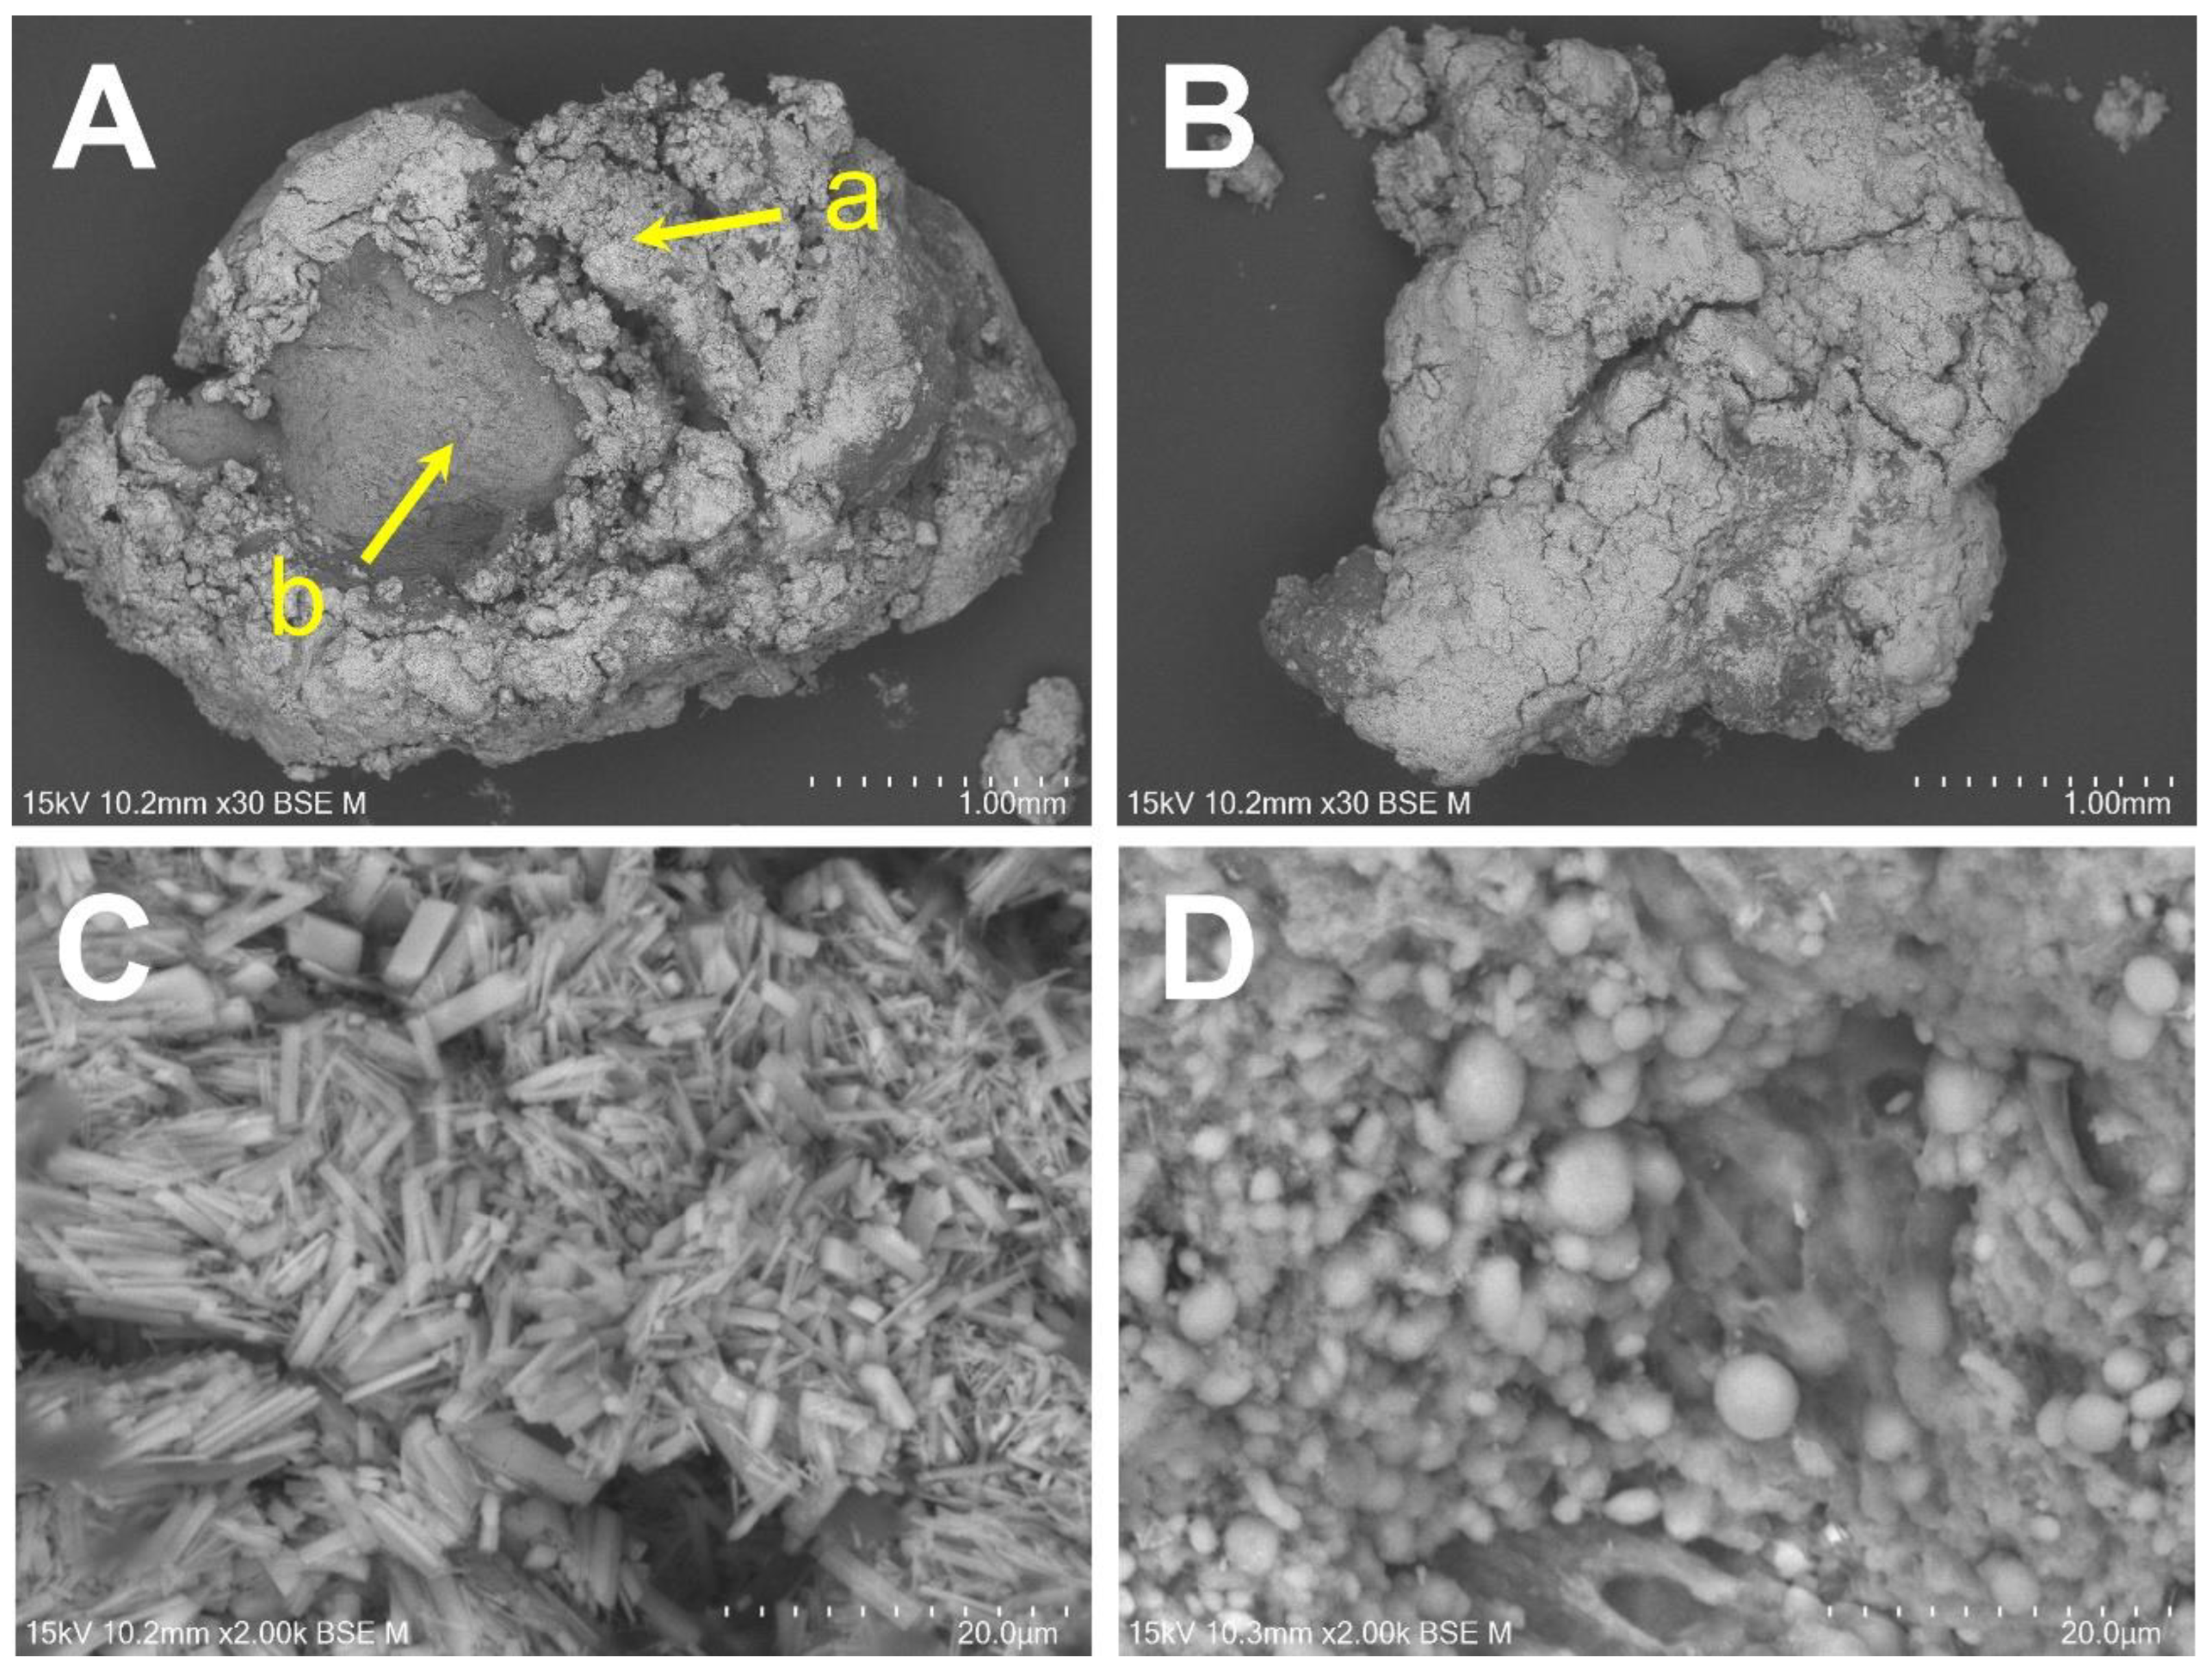

2.3. Elemental Analysis Using SEM/EDS